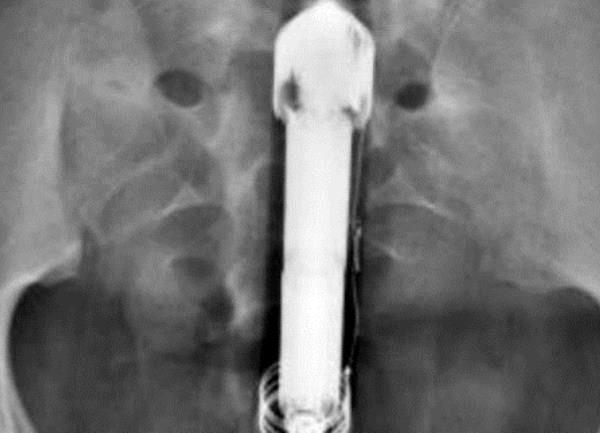

Kako bi dokazao autentičnost svoje priče, korisnik @Grawly je objavio i rentgenski snimak svog abdomena sa vibratorom u svojoj zadnjici i fotografiju CD - a na kojoj se nalaze ostale fotografije i podaci o proceduri koju je prošao u bolnici.